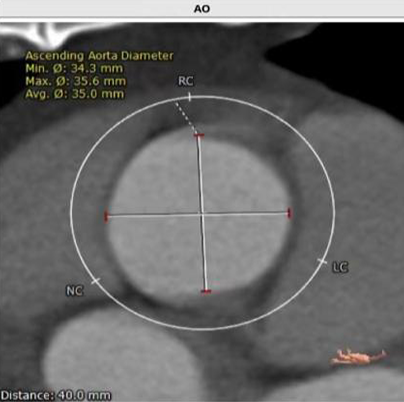

CT

瓣叶分型:三叶瓣 STJ:25.3mm AO:35mm